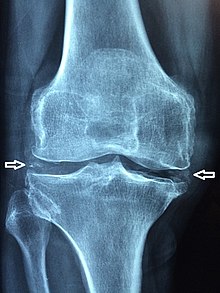

هشاشة #العظام. #الرومتويد. التهاب المفاصل. تاكل #الغضاريف

5• حصوات كلى #تصلب شرايين تكلسات ومشاكل #الركبة والمفاصل ضعف الاسنان هشاشة عظام.